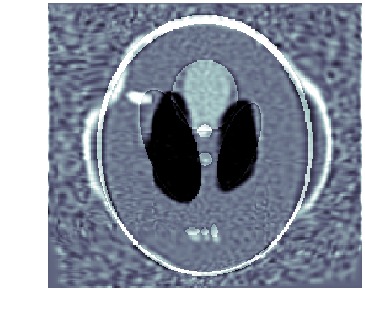

5.4 Inconsistent topology and intensities

Here, both topology and intensities of the template differ from those in the target. The template, which is shown in fig. 3(a), is registered against tomographic data shown in fig. 3(c). The (unknown) target used for generating the data is shown in fig. 3(b). Also, data has a noise level corresponding to a \acPSNR of and kernel size is , which should be compared to the size of the image domain . The final reconstruction is shown in fig. 3(h), which is to be compared against the target in fig. 3(b). Figure 3 also shows image, deformation and template trajectories.

We clearly see that metamorphosis based indirect registration can handle a template where both intensities and the topology are wrong. In particular, we can see follow both the deformation of the template and the appearance of the white disc.